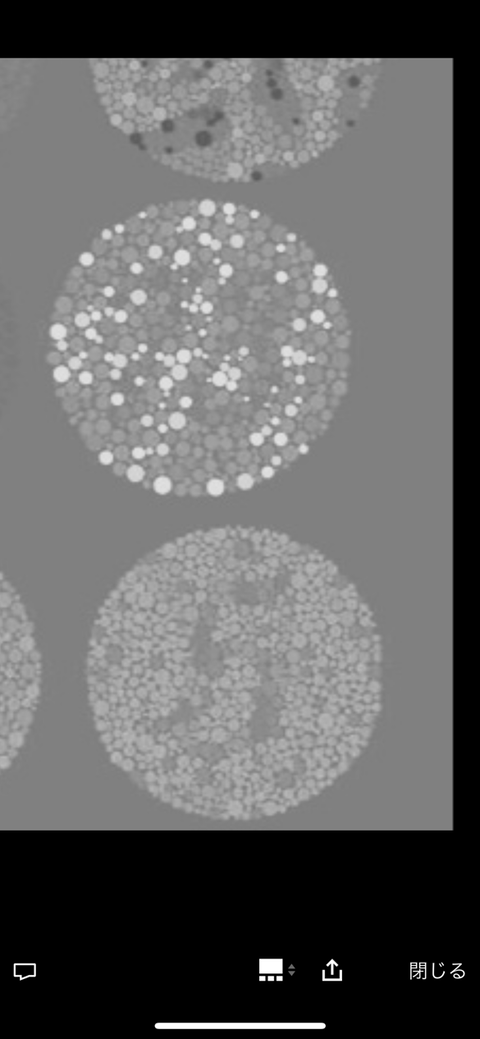

右下わからん

色盲だと数字が見えるやつやで

6.12.73

15.2925

これ読めないって目大丈夫か?

色盲だと多分29のヤツ別の数字に見えると思うわ

6 12 73

15 29 ?

これが正常者の答えな

右下トラップ見える人には何が見えるんやろ

右下見める奴は色弱定期

左下が17、下が70に誘導させたがってるのはわかるんやが、右下は何に見えるのか検討もつかん

ググったら一部の人には5が見えるらしい

赤と緑が全く区別できん人には見えるらしいで

色覚検査的には正常でも外周の色と中央の付近の色で使われてる色の違いを追っていけば右下もなんとなく見えてくるで

小学生のときにクラス全員に一度に見せられて、5個までは皆んな答え一致してて、最後のだけ分かんなくて1人だけ「5」って元気よく答えててみんなすげーすげー言ってたな

今思えばあの子色盲だったのか

みんなまとめて検査するとか残酷な仕方だったな